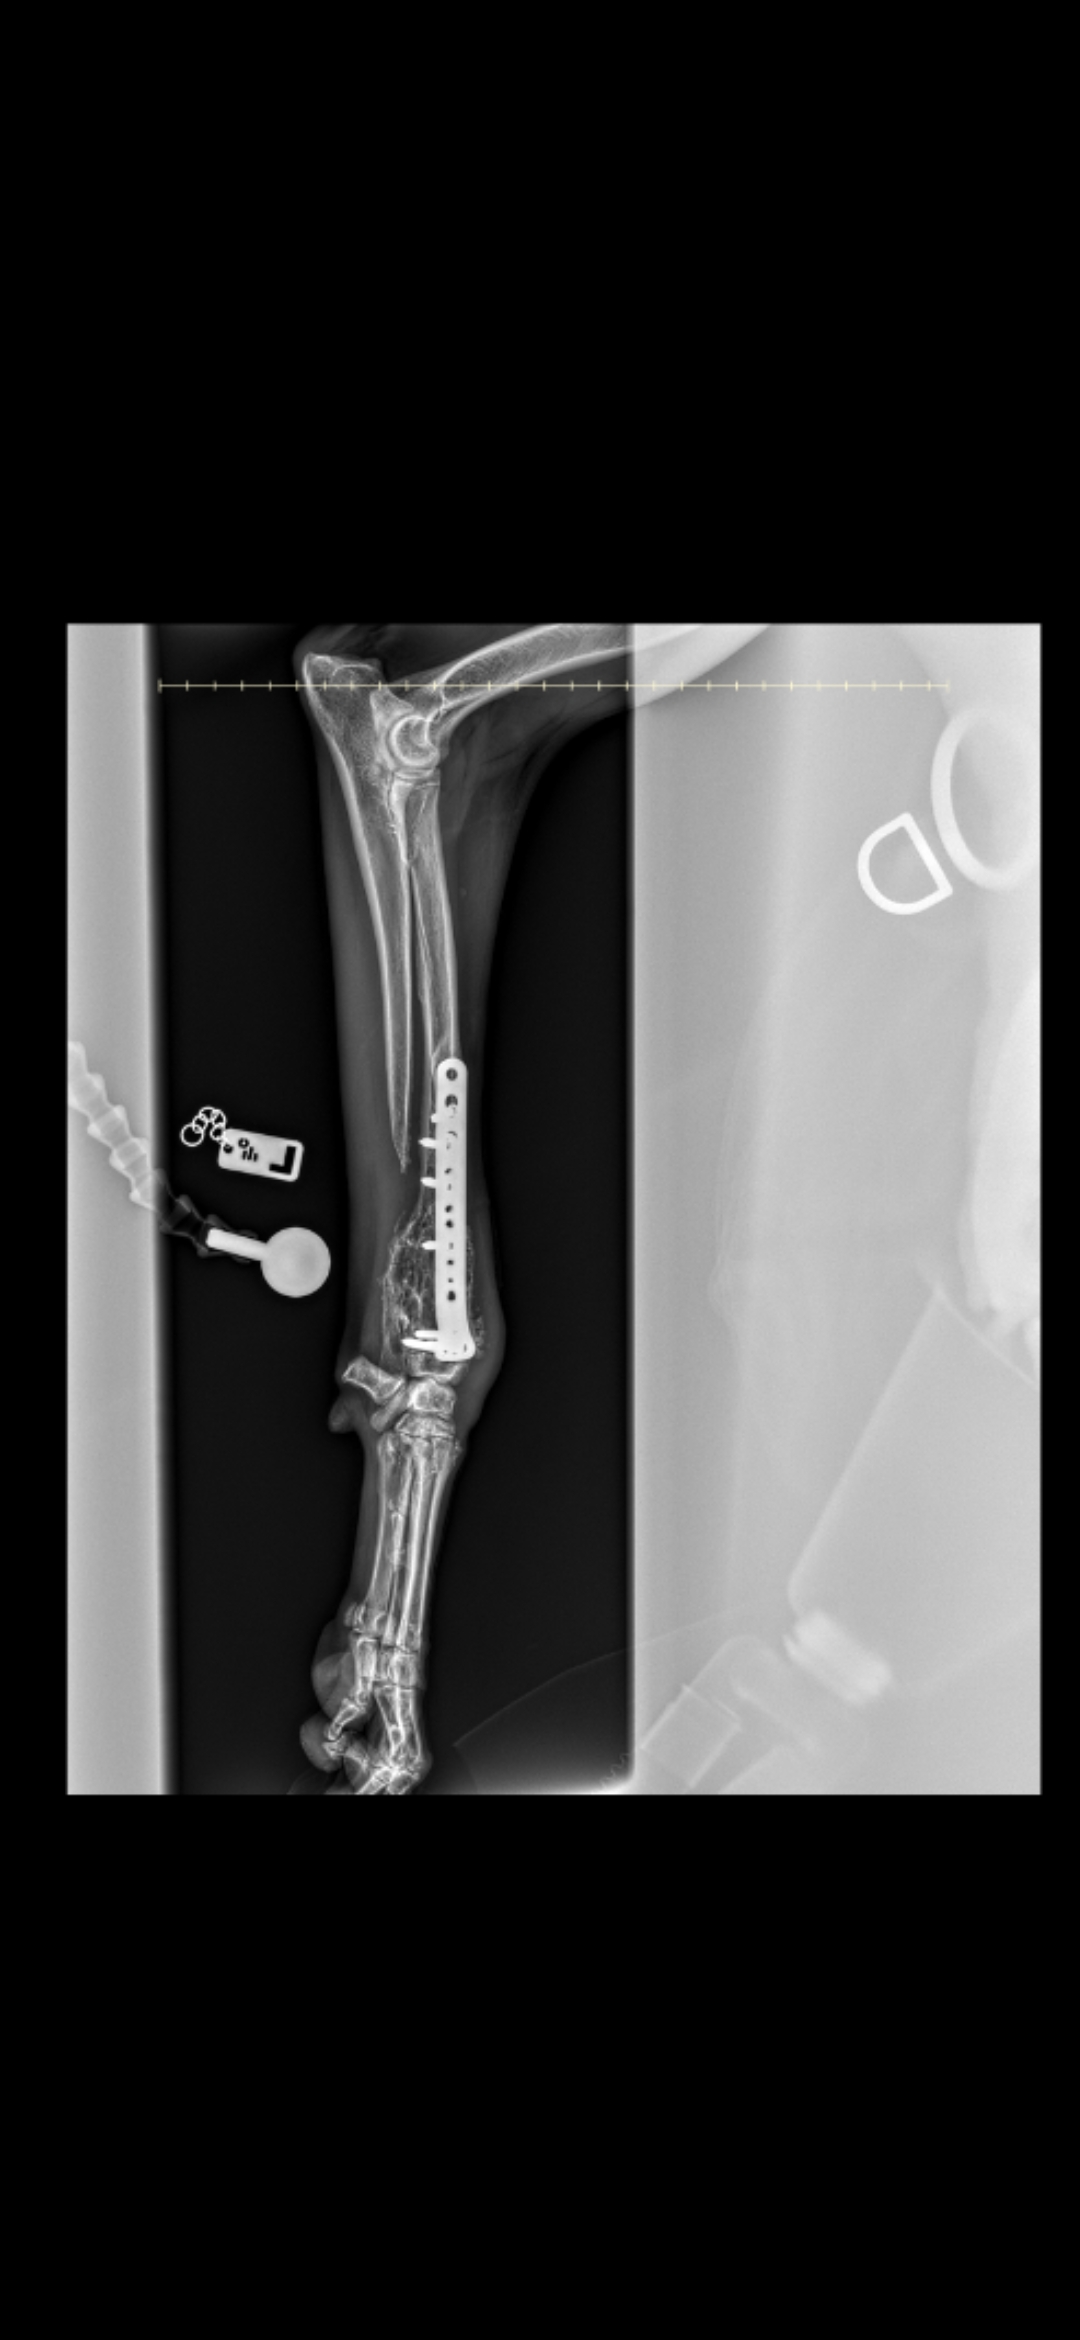

In January 2024, I broke my front leg whilst running with my sister Liberty. I think I caught my paw in a rabbit hole and snapped my ulna and radius bones. I had to have 3 metal plates inserted in my leg to enable the bones too fuse and grow so that I could walk again.

1 year later, I suffered a vascular event (a kind of neurological human stroke). Mum found me splayed on the floor unable to get up. Mum helped me up but found that I was leaning to one side and very unsteady and confused. Off I went to the emergency vet at Langfords who monitored and looked after me in hospital. Whilst I was there, they discovered that I was a bit lame. I made a speedy recovery from the vascular event but was sent to Rowe vet to see what was causing my limp. I had an xray and the vet discovered the aggressive cancer which was eating away the bone in my leg.